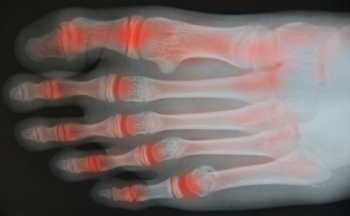

Arthritic pain and stiffness in the toes often develop gradually and can make walking, standing, or wearing shoes uncomfortable. Degenerative joint changes are a common cause, especially with aging, past injuries, repetitive stress, or long-standing foot mechanics that overload small joints. Inflammatory conditions and autoimmune disease may also affect the toe joints. Common signs include aching or burning discomfort, swelling, reduced range of motion, and difficulty pushing off while walking. Some people notice joint enlargement, altered toe position, or increased pain with cold weather or activity. Care focuses on reducing stress through footwear changes, activity modification, and custom orthotics to improve alignment. Anti-inflammatory strategies, targeted exercises, and injections may help manage symptoms. In advanced cases, surgical options can restore function or relieve pain. Early evaluation often prevents progression and protects mobility. If you feel pain or stiffness in your toes, it is suggested that you see a podiatrist for a proper evaluation and treatment options.

Arthritis is a term that is commonly used to describe joint pain. The condition itself can occur to anyone of any age, race, or gender, and there are over 100 types of it. Nevertheless, arthritis is more commonly found in women compared to men, and it is also more prevalent in those who are overweight. The causes of arthritis vary depending on which type of arthritis you have. Osteoarthritis for example, is often caused by injury, while rheumatoid arthritis is caused by a misdirected immune system.

Arthritic symptoms range in severity, and they may come and go. Some symptoms stay the same for several years but could potentially get worse with time. Severe cases of arthritis can prevent its sufferers from performing daily activities and make walking difficult.